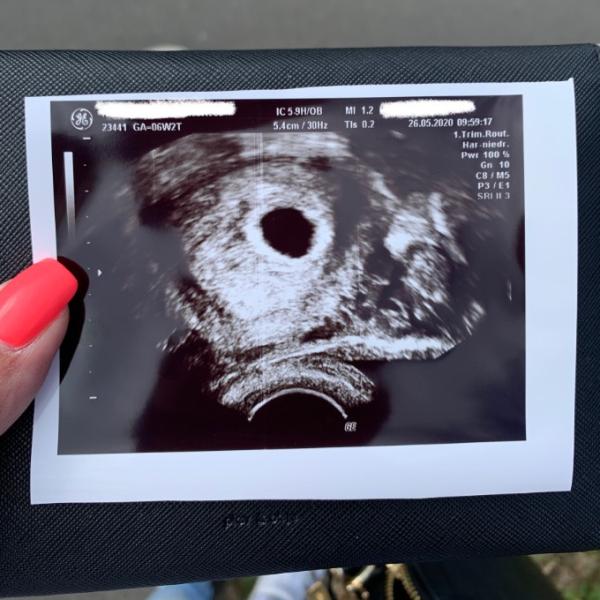

Ich hatte heute erneut einen Termin. Und im Vergleich zum letzten Termin hat sich richtig gut was getan

Letzte Woche war ja nur ein kleiner Punkt zu sehen. Anbei packe ich das heute entstandene Bild rein.

Nach letzter Periode wäre ich 6+2. Das Bild kommt aber eher an 5+2 ran wo auch mein Eisprung war

Nächste Woche geht es erneut zur Kontrolle, da man in der Fruchthöhle selbst nur etwas erahnen konnte aber nicht zu 100%. Das sieht nächste Woche hoffentlich anders aus

Was sagt ihr zum heutigen Bild?